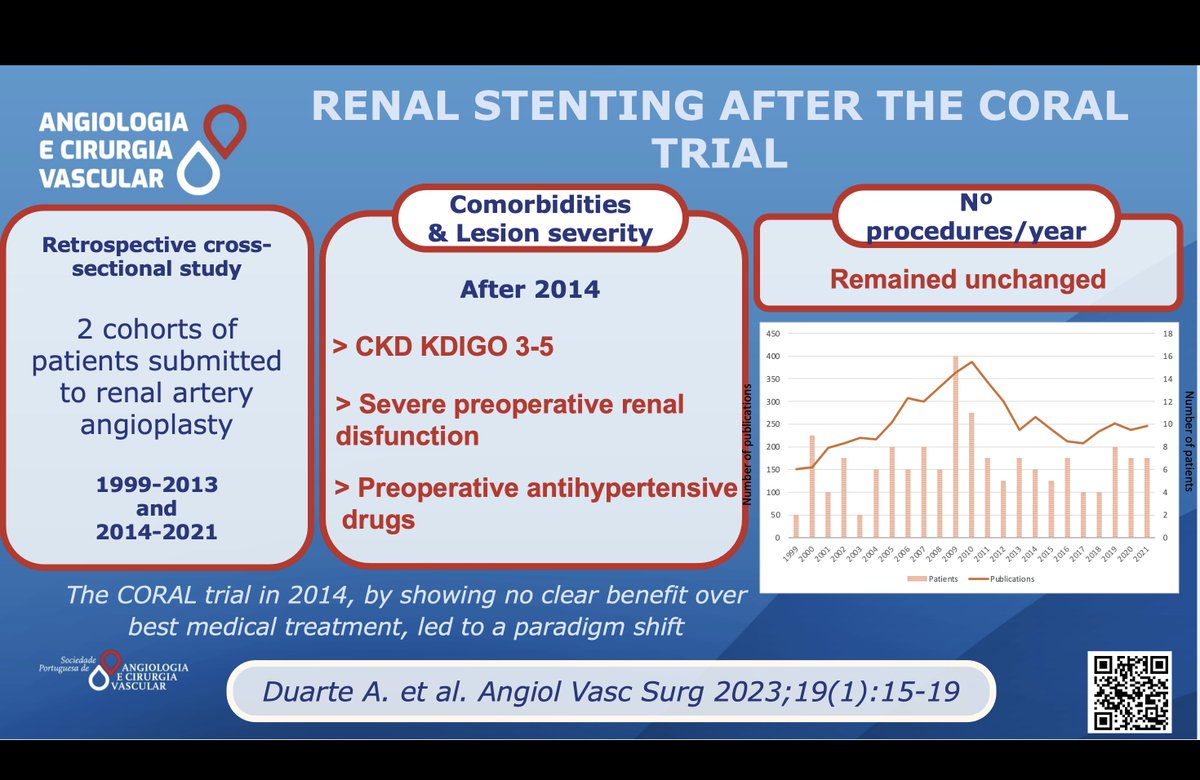

Did the CORAL trial impact your clinical practice? State your opinion below ! #CORALtrial #Renalstenosis #Renalstenting #Renalangioplasty #Vascularsurgery #SPACV @SPACV_ EJVES European Vascular Surgeons in Training (EVST) Vascular SVS Check Duarte A. et al article here acvjournal.com/index.php/acv/…